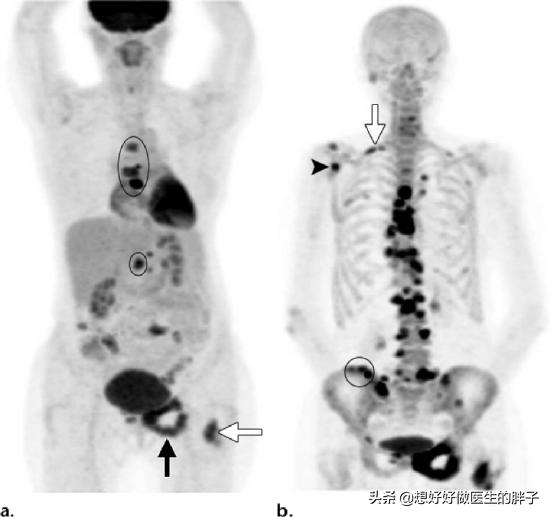

Welche Art von Schmerzen sollten auf eine Knochenmetastase hinweisen? Knochenmetastasen sind eine häufige Erscheinung bei bösartigen Tumoren im Spätstadium, d. h. der Primärtumor ist über Blut- und Lymphbahnen in andere Körperteile eingedrungen und hat dort Knochenmetastasen gebildet. Knochenmetastasen bedeuten, dass normales Knochengewebe zerstört und durch Tumorgewebe ersetzt worden ist. Knochenmetastasen lassen sich je nach Spezifität der Läsion in drei Typen einteilen: osteolytischer Typ, osteogener Typ und Mischtyp. Die häufigsten Stellen, an denen Knochenmetastasen auftreten, sind der mittlere Schaftknochen (Wirbelsäule und Becken), die Rippen und die untere Metaphyse, wobei vor allem der mittlere Schaftknochen am häufigsten betroffen ist, was mit den Eigenschaften der Blutversorgung in diesem Bereich zusammenhängt. Wie im Kreis unten dargestellt, gibt es mehrere Knochenmetastasen und die Wirbelsäule ist in einem schlechten Zustand.

Bei Patienten, die keine Krebsvorgeschichte haben und deren Familie finanziell gut gestellt ist, wird eine PET-CT-Untersuchung empfohlen, um den ganzen Körper auf verdächtige Krebsläsionen zu untersuchen, mit der sich das Vorhandensein von Tumorläsionen, ihr Fortschreiten und die Art der Metastasenherde angemessen feststellen lassen.

Wenn eine Krebserkrankung in der Vorgeschichte vorliegt und der Grad der Bösartigkeit zu diesem Zeitpunkt als hoch eingeschätzt wird, kann das Vorhandensein von Knochenmetastasen durch eine Ganzkörper-Knochenuntersuchung festgestellt werden. Gleichzeitig kann der Grad der Knochenzerstörung am Ort der Metastasen durch eine Magnetresonanzuntersuchung abgeklärt werden.